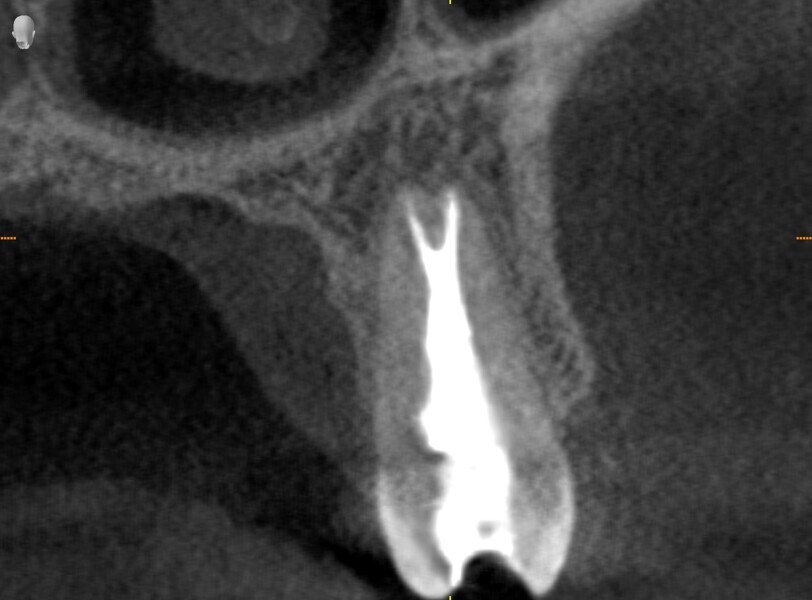

Instrumentation was then performed with the R25 RECIPROC blue up to the level of the split, and the split was prepared with the 12.5/0.04 R-PILOT (VDW; Fig. 18). The final irrigation protocol was performed with copious amount of fluids (sodium hypochlorite and citric acid with a final rinse of distilled water; Fig. 19). Obturation was performed with the piston technique, and the restoration was done with composite material (Fig. 20). The patient was referred to the prosthodontist for final restoration. On the final CBCT scan, it was clearly visible that the piston technique had helped to obturate the deep split in the apical area (Fig. 21).

The patient was referred to Dr Karaś’s office for non-surgical root canal retreatment of tooth #46. The tooth was symptomatic, and the radiographic examination revealed a periapical lesion around the mesial root. The periapical lesion was clearly visible, but the shape of the root canal was not clear (Fig. 22). The examination was extended by CBCT imaging. The CBCT scan revealed internal resorption in the mesiobuccal canal and an isthmus and apical inflammatory root resorption in the apical area of the mesial root (Fig. 23). A cast post and prosthetic crown were also noted.

At this stage, one of the most important decisions had to be made regarding the resorption and isthmus present in the mesial root. On the one hand, in the case of non-penetrating internal resorption, the material of choice is gutta-percha with a sealer. On the other hand, in the case of apical inflammatory root resorption, it is recommended to use mineral trioxide aggregate (MTA) or putty materials. There is no problem with using these two materials in the same root in most cases, but in this case, the canals were too narrow to use the MTA comfortably and the quality of filling of the isthmus that could be achieved was questionable.

From this point of view, a novel approach of placing a tricalcium silicate-based sealer was a promising idea. The sealer was placed in the previously described manner. The premixed sealer in the plastic syringe (Meta Biomed) was placed in the mesiobuccal canal and the syringe depressed until it filled the mesiolingual canal. The distal canal was filled separately. In each canal, pistons from the previously heated gutta-percha extruder were placed and the warm gutta-percha was slightly compacted with stainless-steel hand condensers. A periapical radiograph was taken to evaluate the quality of the obturation. The bioceramic sealer was slightly extruded through the resorbed apex into the periapical area (Fig. 36). After the obturation, the chamber and orifices were cleaned (Fig. 37). A resin core with fibre posts was placed, and the temporary pink material was removed. The patient was referred to the prosthodontist for final restoration.

The recall appointment was performed after three years. The periapical radiograph and CBCT scan revealed healing of the periapical tissue and no resorption of the bioceramic sealer (Fig. 38). The tooth remained asymptomatic.